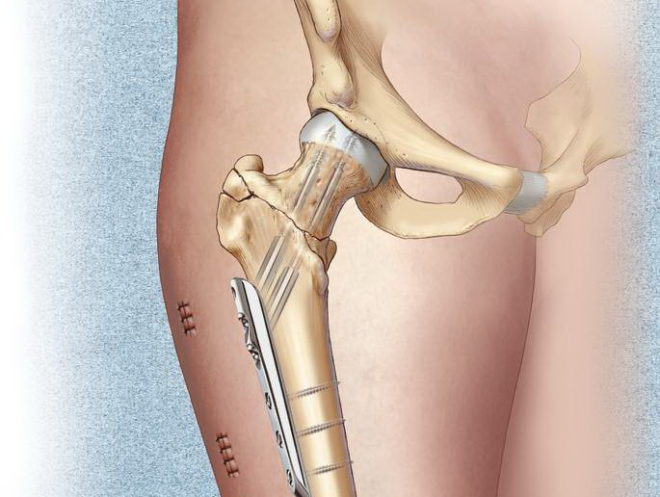

Fontos! Ha egészségügyi okok miatt a művelet engedélyezett egy adott beteg számára, ettől nem utasíthatja. Így jelentősen növeli az esélyét a teljes gyógyulás. Azonnali és hatékony lépéseket, hogy segítsen az egészségügyi személyzet a beteg inkább foglalkoznak sérülések. Ha megfelelően rögzíteni a törött csont fúziós sokkal gyorsabban megy végbe.

A sebészeti eljárás során leggyakrabban elvégzett összehúzódása a csavarokat a sérült terület, amely után teljes helyreállítás hagyni.